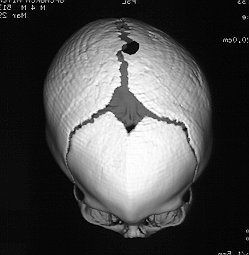

Lambdoidal

• 2-4% of synostoses are true lambdoidal fusions

• unilateral lamdoidal synostosis yields occipital plagiocephaly

• parallelism is a parallelogram-shape induced by longterm

• supine positioning.  The occiput is flattened, and the

diagonally opposite frontal bone bulges.

True Occipital Plagiocephaly Parallelism